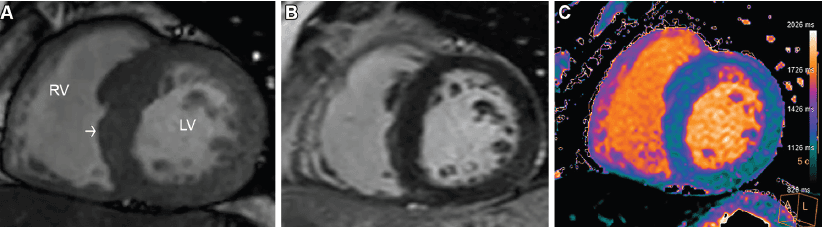

En el atleta, la RM es la herramienta más robusta para distinguir adaptación fisiológica de miocardiopatía o inflamación. Permite evaluar grosor parietal, relación masa-volumen, función biventricular, edema, fibrosis y cicatriz. En el remodelado fisiológico, la hipertrofia suele ser concéntrica, típicamente menor de 16 mm, con proporcionalidad estructural, ausencia de LGE y valores tisulares conservados. En cambio, la presencia de LGE, edema o alteraciones segmentarias obliga a abandonar la etiqueta de “corazón de atleta” como explicación automática. Incluso en zonas grises, la proporcionalidad importa más que el grosor aislado.

Dos escenarios del paper concentran el mayor valor narrativo del blog. Primero, la miocarditis: la combinación de LGE subepicárdico o mesomiocárdico con elevación de T1 y T2 cumple criterios de Lake Louise y redefine temporalidad, riesgo y retorno al deporte. Segundo, las anomalías coronarias: el origen anómalo con trayecto interarterial e intramural puede ser silente en reposo, pero volverse crítico durante el ejercicio. El artículo subraya que estas anomalías se asocian con un riesgo 79 veces mayor de arritmia con el esfuerzo. Esa es la diferencia entre una imagen interesante y una imagen clínicamente decisiva.